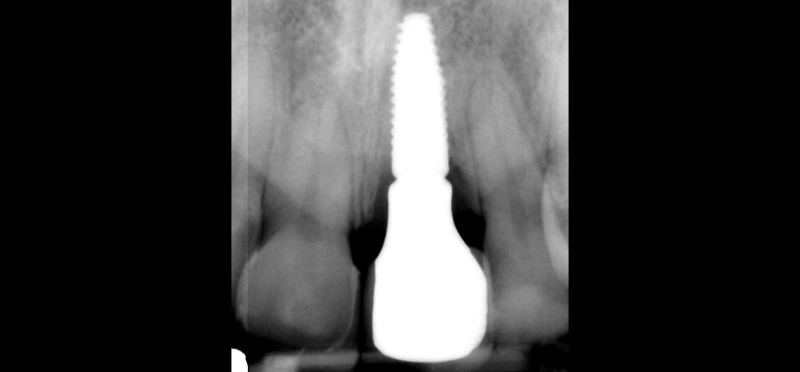

Customized Impression Coping for a Single Tooth Implant in a Maxillary Central Incisor

The esthetic success of an anterior implant-supported restoration mostly depends on having a soft-tissue architecture indistinguishable from the adjacent teeth. One of the most critical steps to achieve this “esthetic success” is correctly using the provisional restoration to optimize and properly contour (groom) the peri-implant tissue anatomy.

Once the optimal emergence profile has been developed, we need to communicate and transfer this information properly to the laboratory. Unfortunately, all implant companies provide stock round impression copings that do not precisely transfer the soft-tissue contours. A simple protocol to communicate this information is described here.

This visual essay walks through a step-by-step description of how to fabricate a personalized impression coping with transfer ofthe peri-implant tissue anatomy properly.